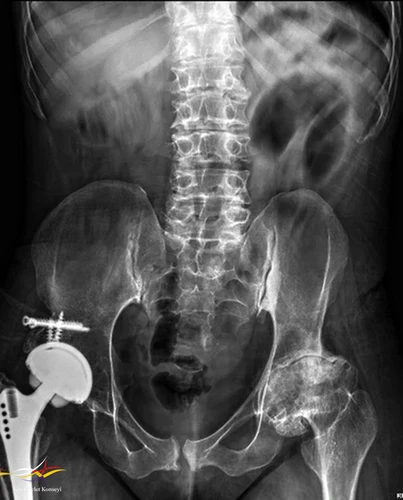

Resim 2.

Hikayesinden 5 yaşında coxa vara nedenli diz operasyonu (3 kez tekrar edilmiş), yaşını hatırlayamadığı bacak boyu uzatma operasyonu (çocukluk döneminde), 11 yaşında omuz cerrahisi (etyoloji aydınlatılamadı), 32 yaşında sağ kalça protez operasyonu öyküsü var.

Femur başında: Kısa femoral boyun, coxa vara, kalça çıkığı veya düzensiz epifizyal konturlar.